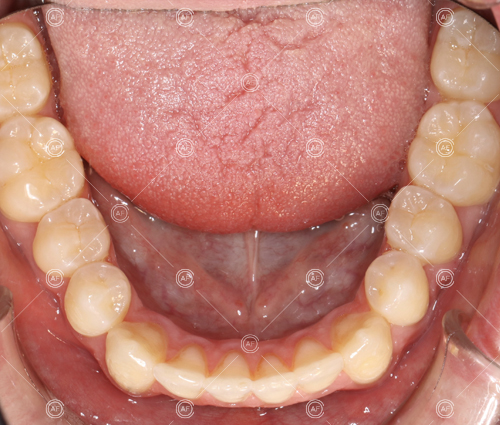

This patient (MH) began her active orthodontic treatment in October 2019 at almost 13 years old. She was unhappy with the appearance of her upper and lower teeth, and especially concerned about the unsightly nature of the high and buccally positioned upper left canine.

about this case…MH presented with class 1 incisors on the class 1 skeletal base with a slightly increased vertical proportion. She had severe crowding in the upper arch and moderate crowding in the lower. Due to the crowding in the lower arch, the lower centre line was off to the left by 2mm.

Buccal segments were essentially class 1 on the right hand side and a full unit class 2 on the left. This is due to buccal exclusion of the upper left 3 and mesial drift of the upper buccal segment.